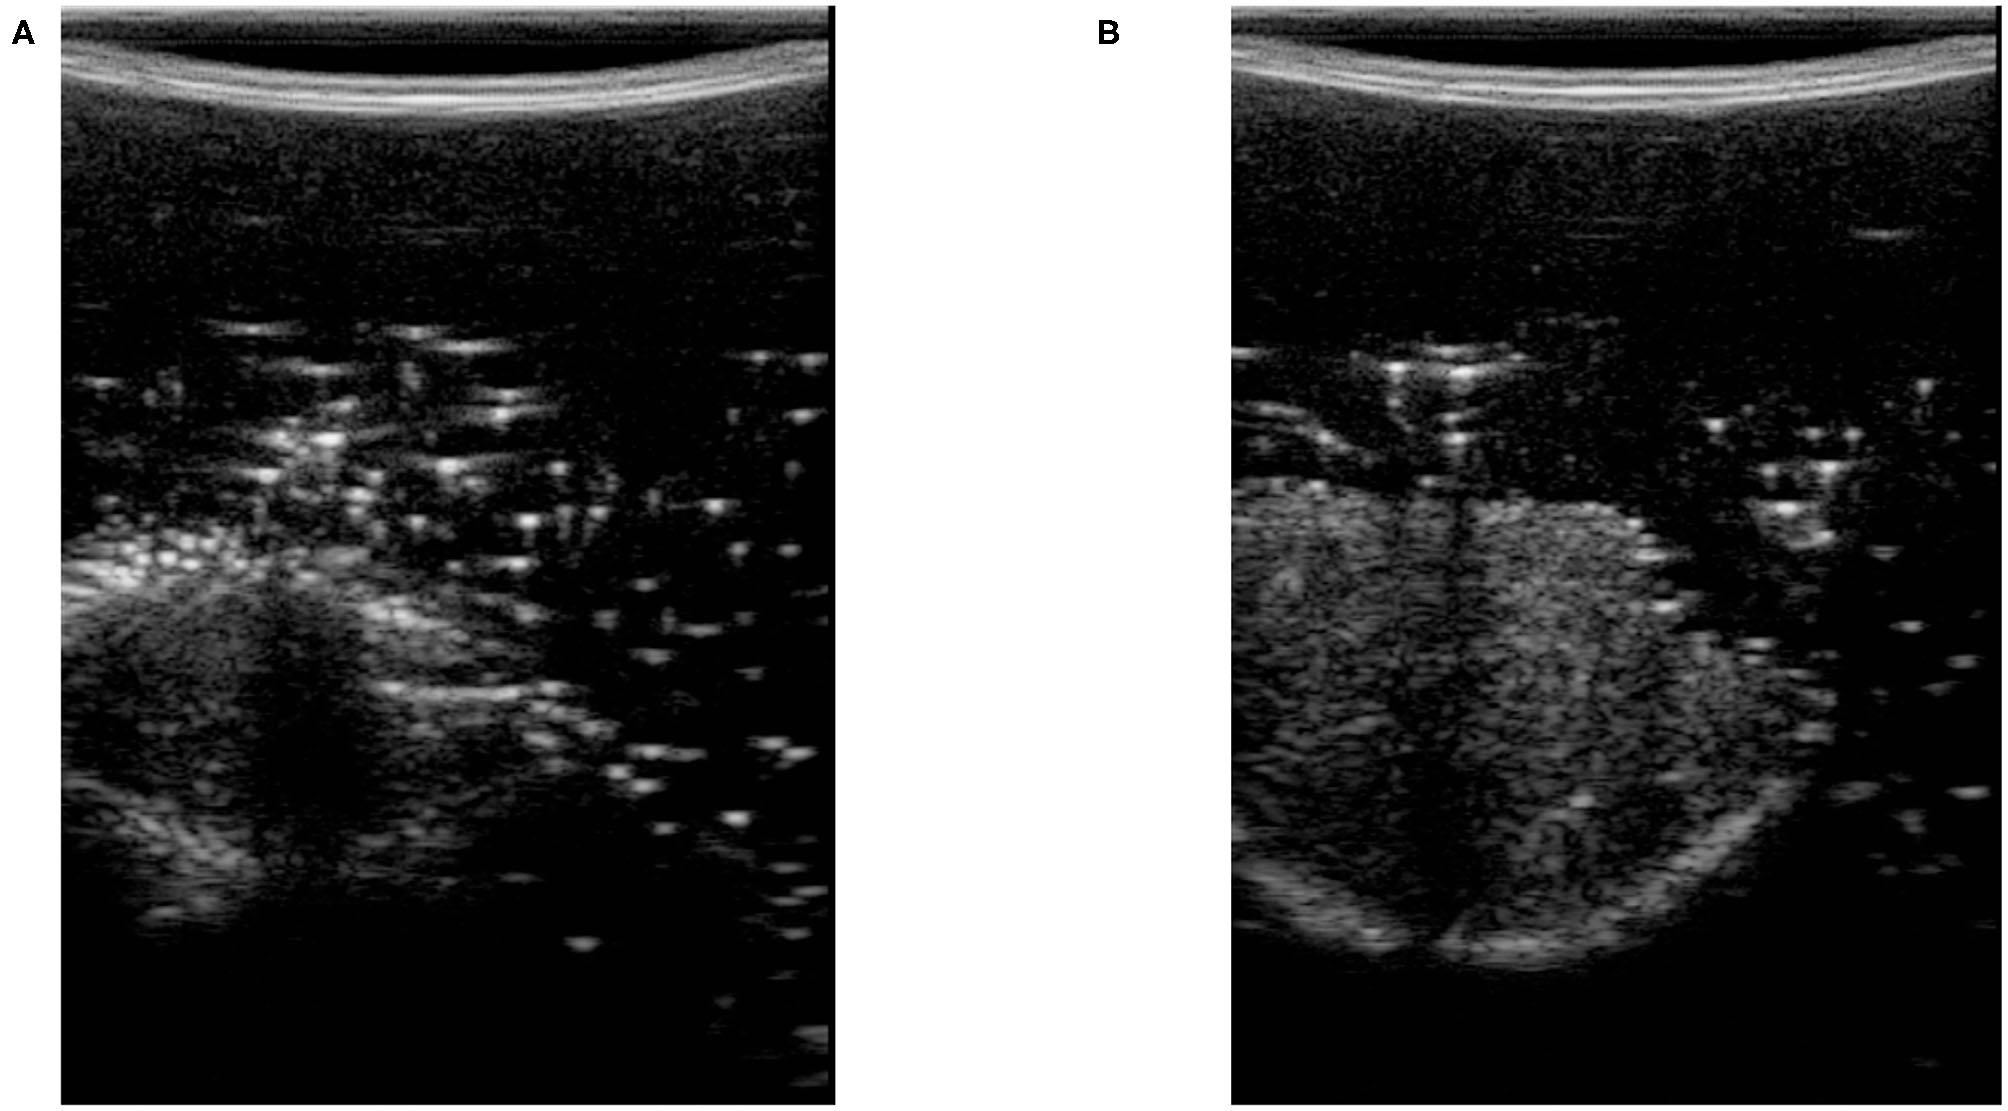

In (3), U and L are the maximum and minimum location of the pixels having intensity higher than tcomp. We define fc as the compression feature in (3). M is the height of the image along the y direction. Figure 3 shows two images with different levels of compression. Figure 3A is the US image with a high level of compression, and Figure 3B is the US image with a low level of compression. We have also shown a variation of fc with respect to measured force in the z direction of the force sensor frame FZ|k (this is aligned with the y direction in image frame) in Figure 4.

Figure 3

Ultrasound images with high and low level of compression. (A) Ultrasound image with high tissue compression. (B) Ultrasound image with low tissue compression.